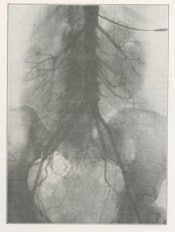

In 1929, Moniz's surgical colleague Reynaldo dos Santos, a professor of surgery in Lisbon, introduced percutaneous translumbar aortography (TLA) by direct aortic puncture with injection of a sodium iodide solution. Three years later, Santos described the technique (figs. 5 and 6). Fig. 7 shows abnormal vascularity in a sigmoid tumor; note the stationary grid lines.

Left, fig. 5: Dos Santos (1932). Right, fig. 6: Technique of aortography (1932).